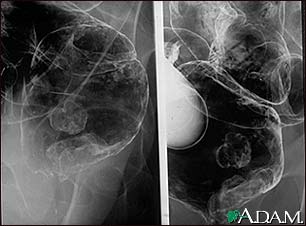

Rectal cancer, X-ray

A barium enema in a patient with cancer of the rectum.